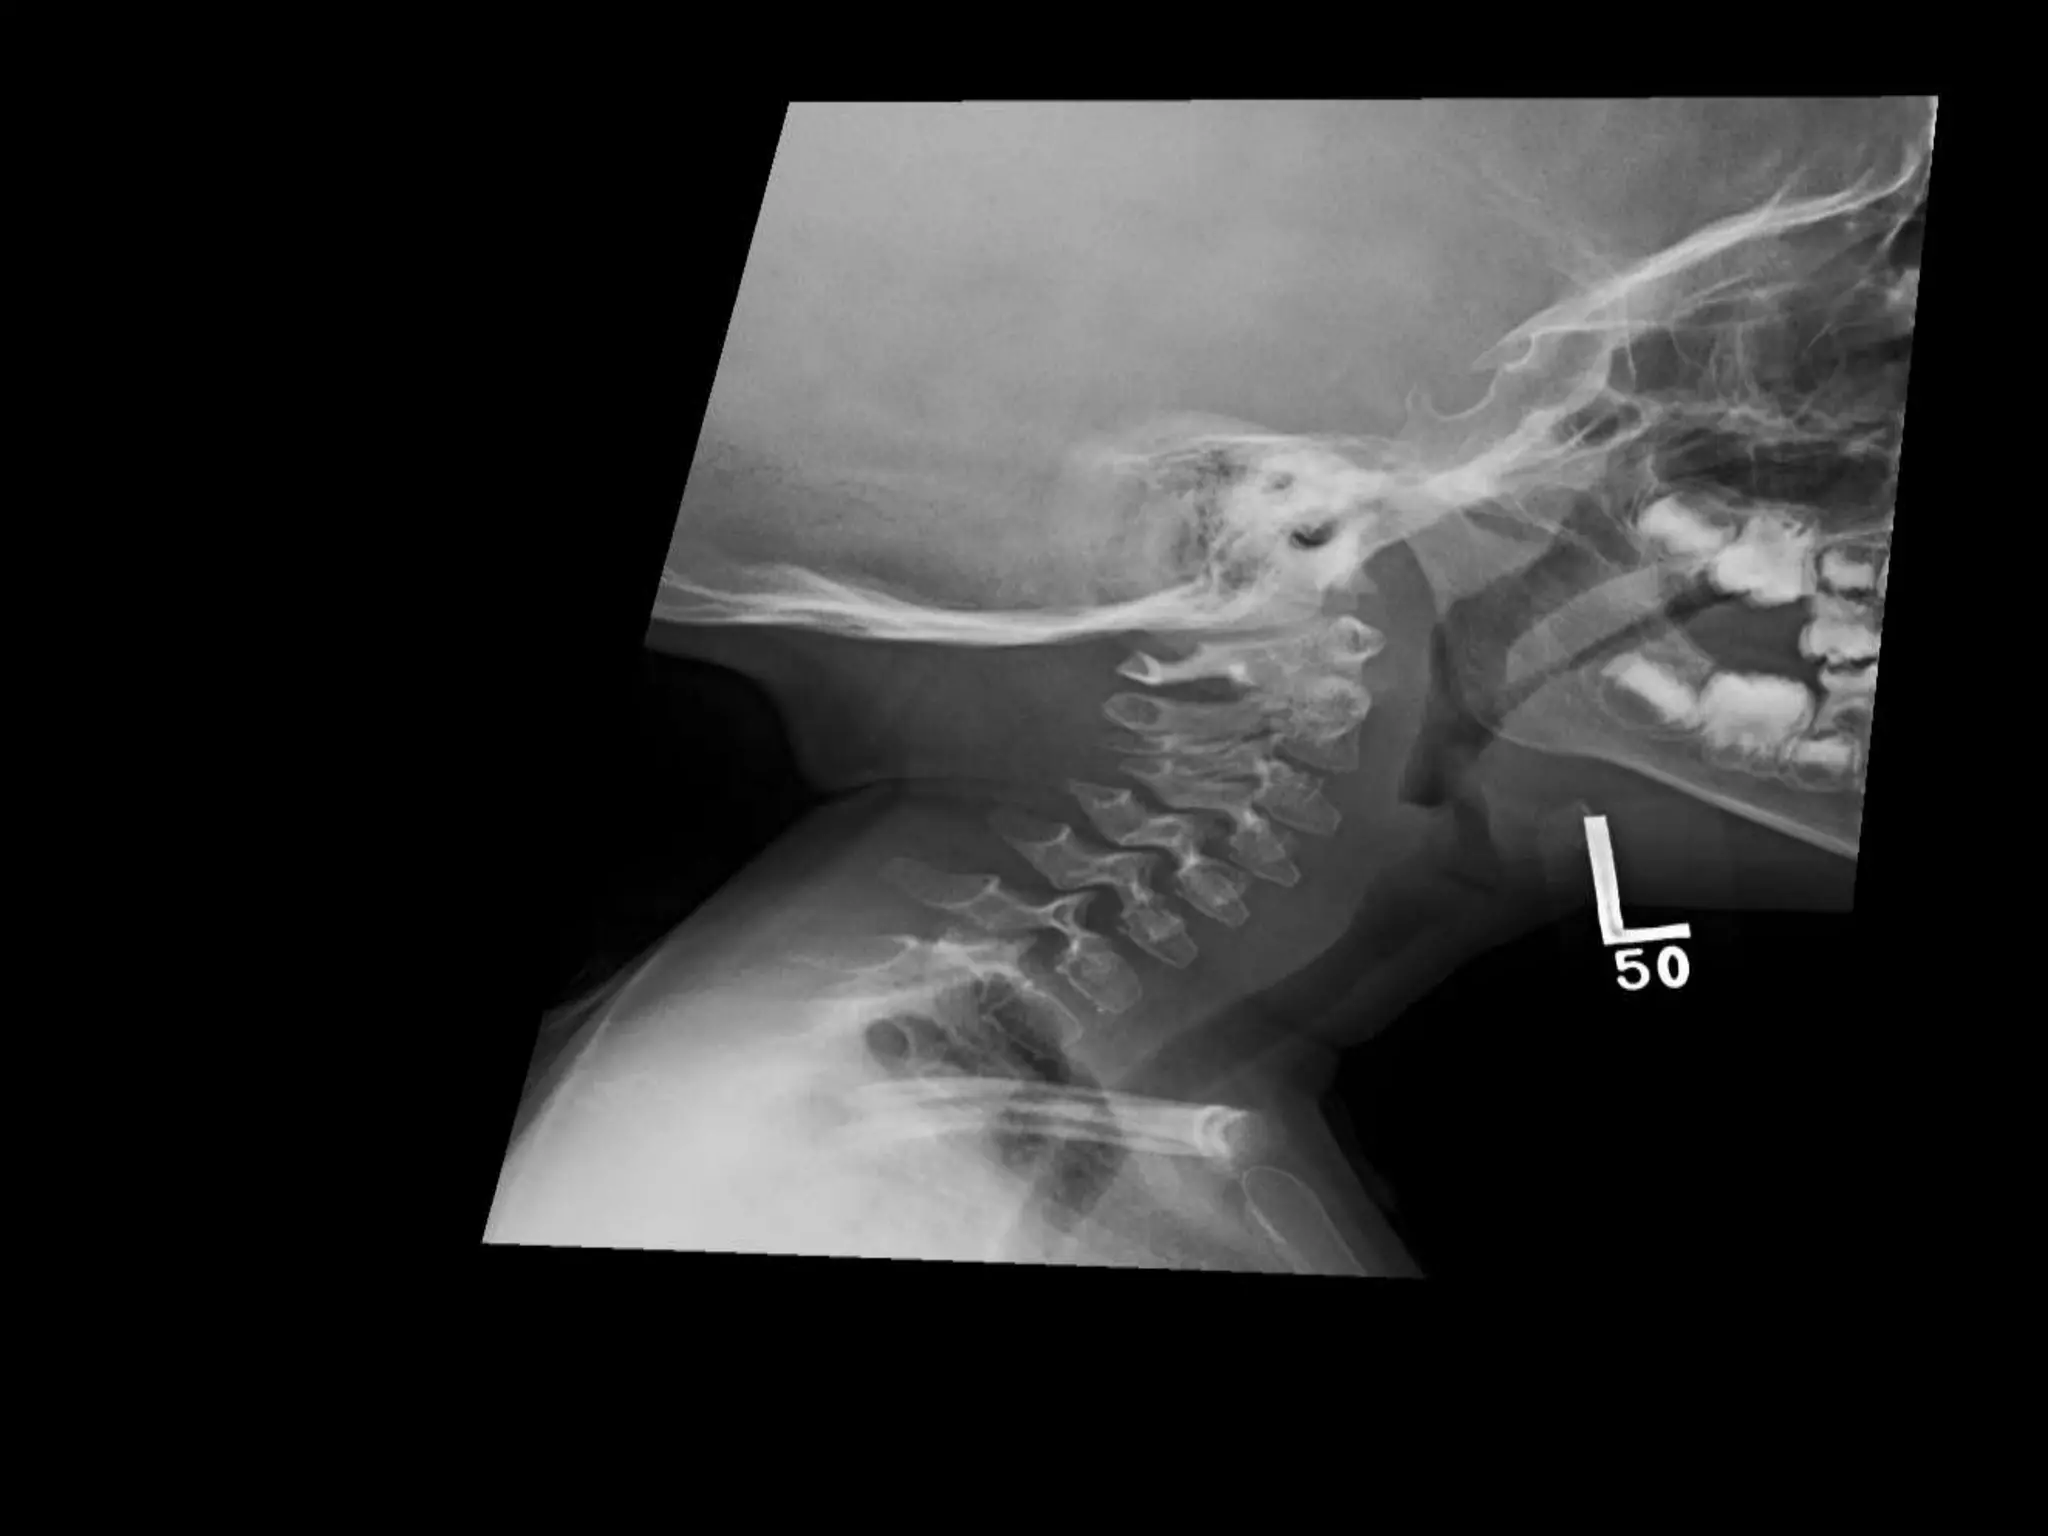

PYKNODYSOSTOSIS

• Short stature

• Frontal bossing

• Mandible underdevelopment

• Abnormal dentition

• X-Ray: skull enlarged with wide sutures/ open

fontanellae

• Facial/mandible hypoplastic --- triangled facies

• 70.

PYKNODYSOSTOSIS • Short stature •Frontal bossing • Mandible underdevelopment • Abnormal dentition • X-Ray: skull enlarged with wide sutures/ open fontanellae • Facial/mandible hypoplastic --- triangled facies